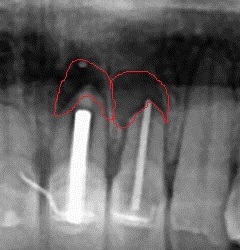

치근단절제술 하긴 전 병변 사진 (붉은색으로 표시)

(위 그림) 붉은색으로 표시된 부위의 치아 뿌리 부분의 염증조직 (아래 그림) 치근단 절제술로 제거 후 뼈이식술 함께 진행된 방사선 사진

(왼쪽) 치아 뿌리 병변 조직 확대 / (오른쪽) 치근단 절제술 + 뼈이식 후 x-ray